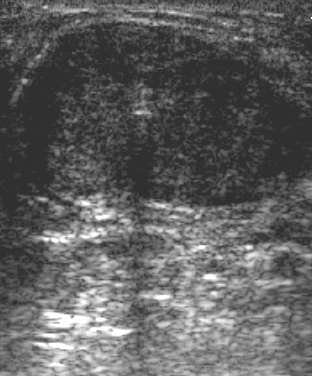

| Ultrasound images during cryoablation showing an ice-ball formation with a cryoprobe through the center of fibroadenoma. Above, longitudinal axis; below, transverse axis. Images courtesy of Dr. Dennis R. Holmes, breast surgeon and director of new technology development, University of Southern California/Norris Comprehensive Cancer Center and Hospital, and chief, breast service, LAC+USC Medical Center, Los Angeles. |

Ultrasound-based breast procedures improve accuracy and efficiency, expand treatment options, and expand billable services "at a time of rising practice expenses and declining reimbursements," said Dr. Dennis Holms, director of new technology development and a breast surgeon at the USC center.